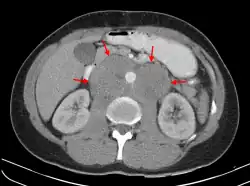

| A CT scan of axillary lymphadenopathy in a 57-year-old man with multiple myeloma. | |

Lymphadenopathy of the axillary lymph nodes can be defined as solid nodes measuring more than 15 mm without fatty hilum.[36] Axillary lymph nodes may be normal up to 30 mm if consisting largely of fat.[36]